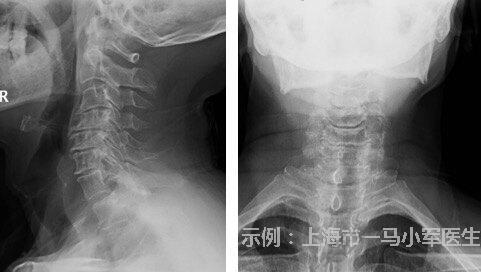

椎管內(nèi)腫瘤

治療前62歲男性患者,因“頸痛2年,加重伴右上肢麻木無(wú)力3月”入院,患者2年前無(wú)明顯誘因下出現(xiàn)頸部疼痛,自行服用止痛藥物、膏藥等(具體不詳)。3月前無(wú)明顯誘因下出現(xiàn)頸痛賈總伴有右上肢麻木無(wú)力,就診于當(dāng)?shù)?,予以塞來昔布、甲鈷胺片、七葉皂苷鈉片治療1月后無(wú)明顯好轉(zhuǎn)。行頸椎MRI掃描提示C3/4椎管內(nèi)硬膜下占位病變,患者為求進(jìn)一步治療,轉(zhuǎn)至上海市第一人民醫(yī)院骨腫瘤科就診,門診擬以“頸椎椎管內(nèi)腫瘤”收治入院。治療后治療后1年患者術(shù)前頸痛癥狀完全緩解,肢體麻木癥狀消失,恢復(fù)至完全正常生活狀態(tài)。